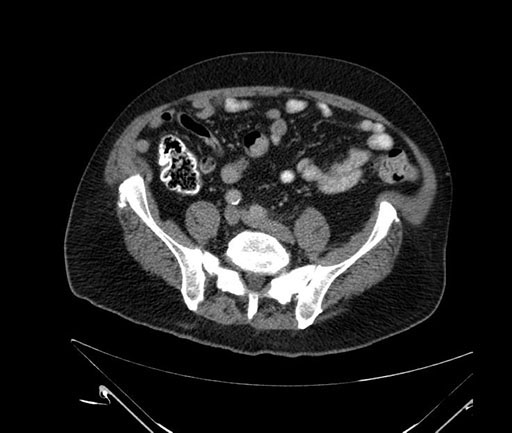

Imaging Analysis

Look through the patient's CT scan to identify any areas of concern for the necessary procedure.

Based on your CT findings, which issue(s) would give reason for "planned slowing down moment(s)" in this case?

Considering a standard Whipple procedure, what step(s) of the operation would you do differently in this case?